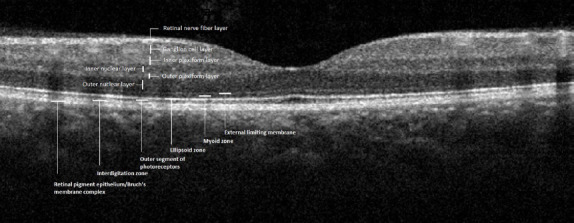

There has been progressive growth in the use of SD-OCT in ophthalmology. The RTVue-100 OCT scanner (Optovue Inc., Fremont, CA, USA) was used to measure the thickness of the central macula, RNFL, and GCC in both study groups. The RTVue-100 can perform 26,000 A scans per second with a depth resolution of 5 µm (23). The central macular and RNFL thickness measurements were performed using the 5-mm macular map and an optic nerve head scan, respectively. The GCC comprises the RNFL, the inner plexiform layer and the retinal ganglion cell layer (24), and a GCC scan was used to measure the thickness of this composite layer. A single clinician performed the evaluation and image capture for the study group after pupillary dilation with tropicamide drops. Scans with a signal strength index of <45 or motion artifacts were excluded. An OCT image obtained from the retina of an individual with red-green CVD is shown in Figure 1, and an OCT image obtained from the retina of a control subject is shown in Figure 2. The thicknesses of the central macula, RNFL, and GCC were calculated and used for statistical analysis. Quantitative data obtained from these measurements were compared between Group 1 and Group 2.

Figure 1.

Grey-scale optical coherence tomography image revealing the retinal layers of an individual with red-green color vision deficiency.